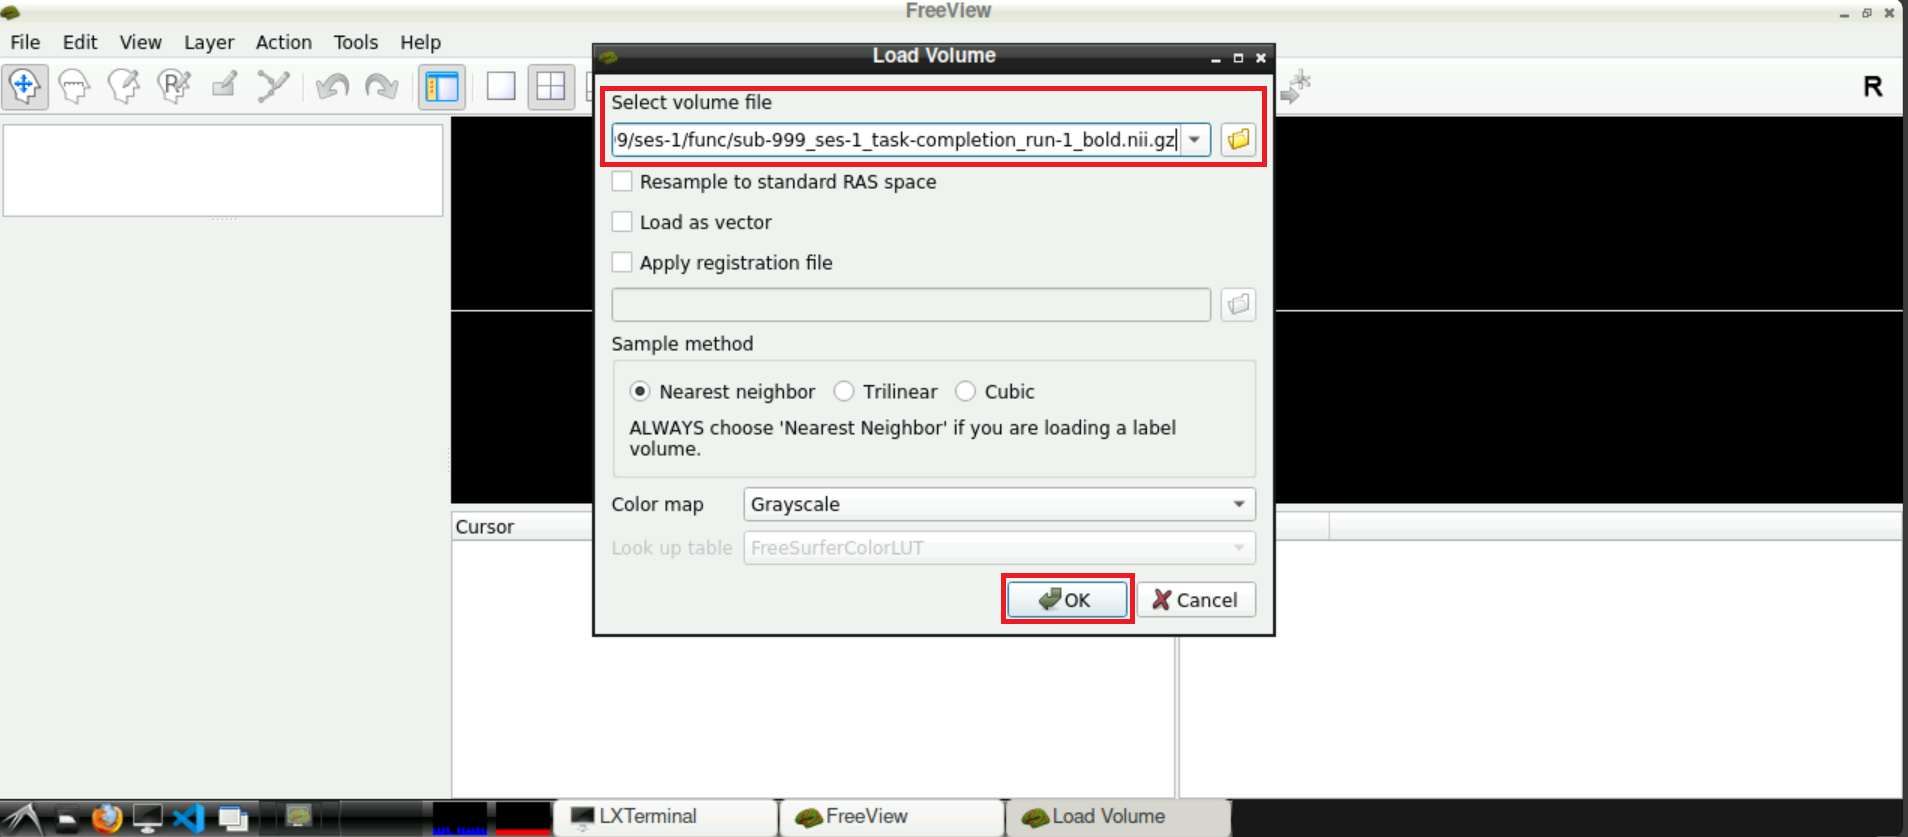

Now, with the field Select volume file specified with the path(s) to the nifti file, you can click Open